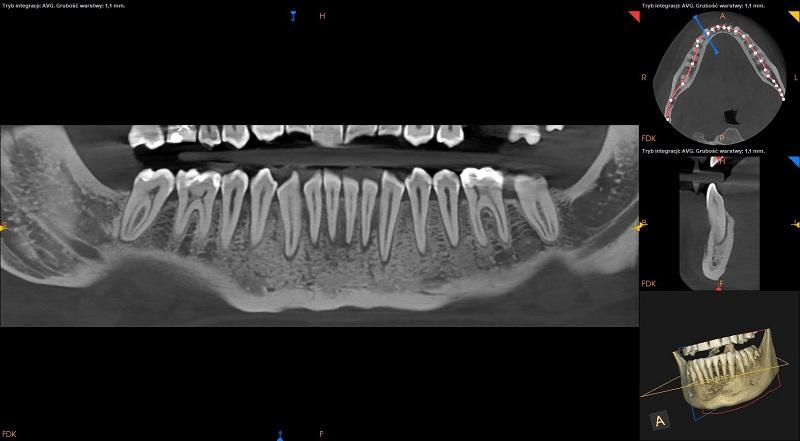

Pacjentka: wiek 25 l.

Badanie z dnia: 02.12.2020

CBCT żuchwy.

Dane kliniczne : przewlekły ból okolicy 33-43

Obraz radiologiczny ukazuje zmiany w przednim odcinku kości żuchwy obejmujące kość części zębodołowej w okolicy zębów 33-43 oraz zmiany w kości spojenia żuchwy.

W kości przyzębia obserwowane częściowa resorpcja blaszki zbitej zębodołu.

Wyraźne poszerzenie ozębnej brzeżnej.

Niszczenie rozpoczyna się w połowie długości korzeni zębów i biegnie w kierunku brzegu wyrostka.

Obraz destrukcji kostnej jak w przebiegu agresywnego zapalenia przyzębia.